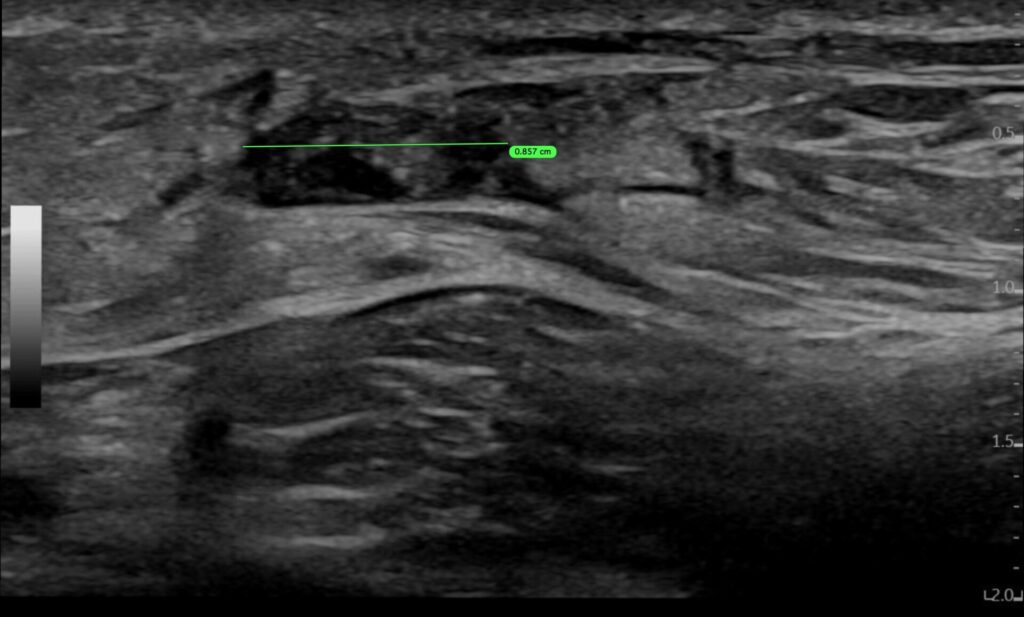

3. Diastase der Sehnenstümpfe

- Beurteilung in Neutralstellung

- Beurteilung in maximaler Plantarflexion

- Restadaptation vollständig? ☐ ja ☐ nein

Die Achillessehne zeigt eine Kontinuitätsunterbrechung im Bereich der mid-portion / des muskulotendinösen Übergangs / insertional. Die Sehnenenden erscheinen glatt / fransig und gegebenenfalls retrahiert. In Neutralstellung besteht eine Diastase der Sehnenstümpfe. In Plantarflexion zeigt sich eine Annäherung der Sehnenenden mit vollständiger / unvollständiger Adaptation.